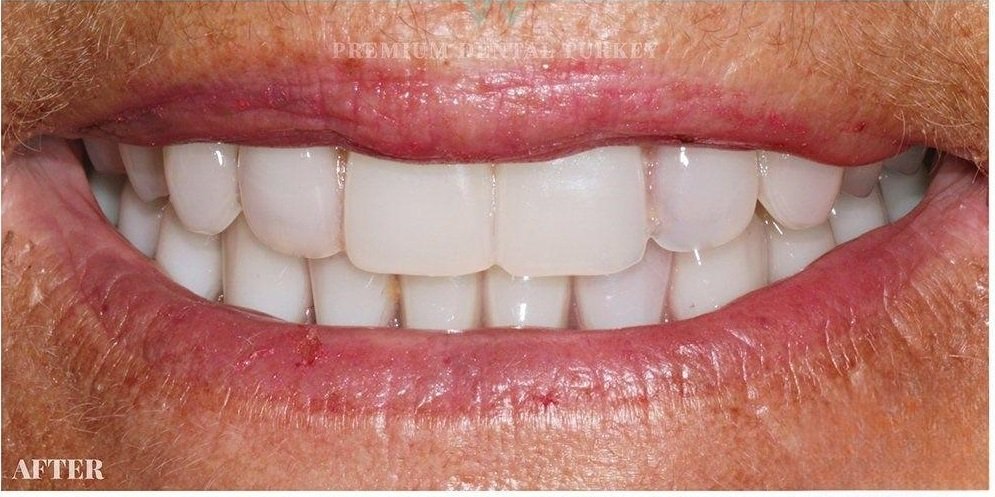

Rudra Dental Clinic, located in Hadapsar, Pune, is a trusted destination for comprehensive and advanced dental care. Led by Dr Disha K. Prajapati, who brings over 19 years of clinical experience, the clinic is committed to delivering high-quality treatments with a patient-first approach. From routine dental checkups and teeth cleaning to specialized procedures like root canal treatment, dental implants, braces, and smile designing, every service is provided with precision, care, and modern technology. The clinic focuses on maintaining hygiene, safety, and a comfortable environment for patients of all age groups.

At Rudra Dental Clinic, the goal is not just to treat dental problems but to create healthy, confident smiles. Dr Disha K. Prajapati and her team take time to understand each patient’s needs and offer personalized treatment plans that ensure long-term oral health. Known for painless procedures and transparent consultation, the clinic has built strong trust among patients in Hadapsar and nearby areas. Whether it’s preventive care or cosmetic dentistry, Rudra Dental Clinic stands as a reliable choice for complete dental solutions..

We always take care of your smile

With experienced care by Dr. Disha Prajapati, modern technology, painless procedures, and patient-focused treatment, Rudra Dental Clinic is a trusted choice for dental care in Hadapsar.